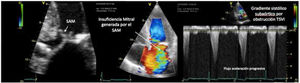

Uno de los cuadros clínicos más difíciles de manejar en el PC es la insuficiencia mitral que se produce por un movimiento anómalo de la valva anterior (SAM), generando un gradiente de presión en el TSVI o mesoventricular, arrastrando y succionando la valva anterior mitral (fig. 3). Debe sospecharse en casos con hipertrofia concéntrica, miectomía o implante de prótesis mitral con postes grandes que se dirigen hacia el TSVI, estados de hipovolemia y/o necesidad de soporte vasoactivo ascendente sin respuesta tensional apropiada.

PC de bypass coronario en paciente con hipertrofia del VI concéntrica: obstrucción dinámica TSVI por exceso de soporte inotrópico e hipovolemia postoperatoria, generando insuficiencia mitral severa por movimiento septal anterior (SAM). Obsérvese el flujo de aceleración progresiva por Doppler continuo.